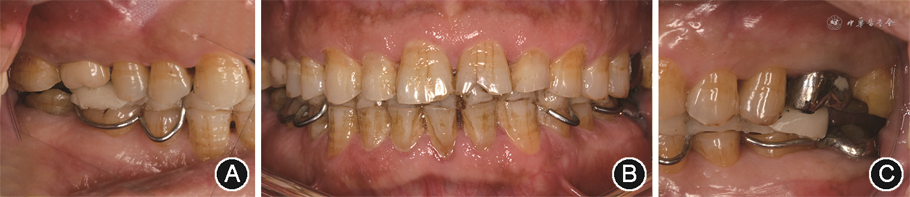

(2)口内检查:全口牙齿不同程度磨损,21呈“V”形缺损,17、15—25、27、36—44、46、47切端或

面及舌侧牙釉质磨损,继发性牙本质暴露,

面存在杯状磨耗小面。16、26全冠修复,37种植固定义齿修复,47

面树脂充填。45缺失,无缺牙间隙。全口多数牙齿探(+/-),冷刺激(-),叩诊(-)。软垢(+),牙石(+),色素(++),局部牙龈充血红肿。全口牙齿无松动,牙周探诊深度2~4 mm。上中切牙中线正,下中切牙中线左偏1 mm,下前牙区散在间隙(图2)。